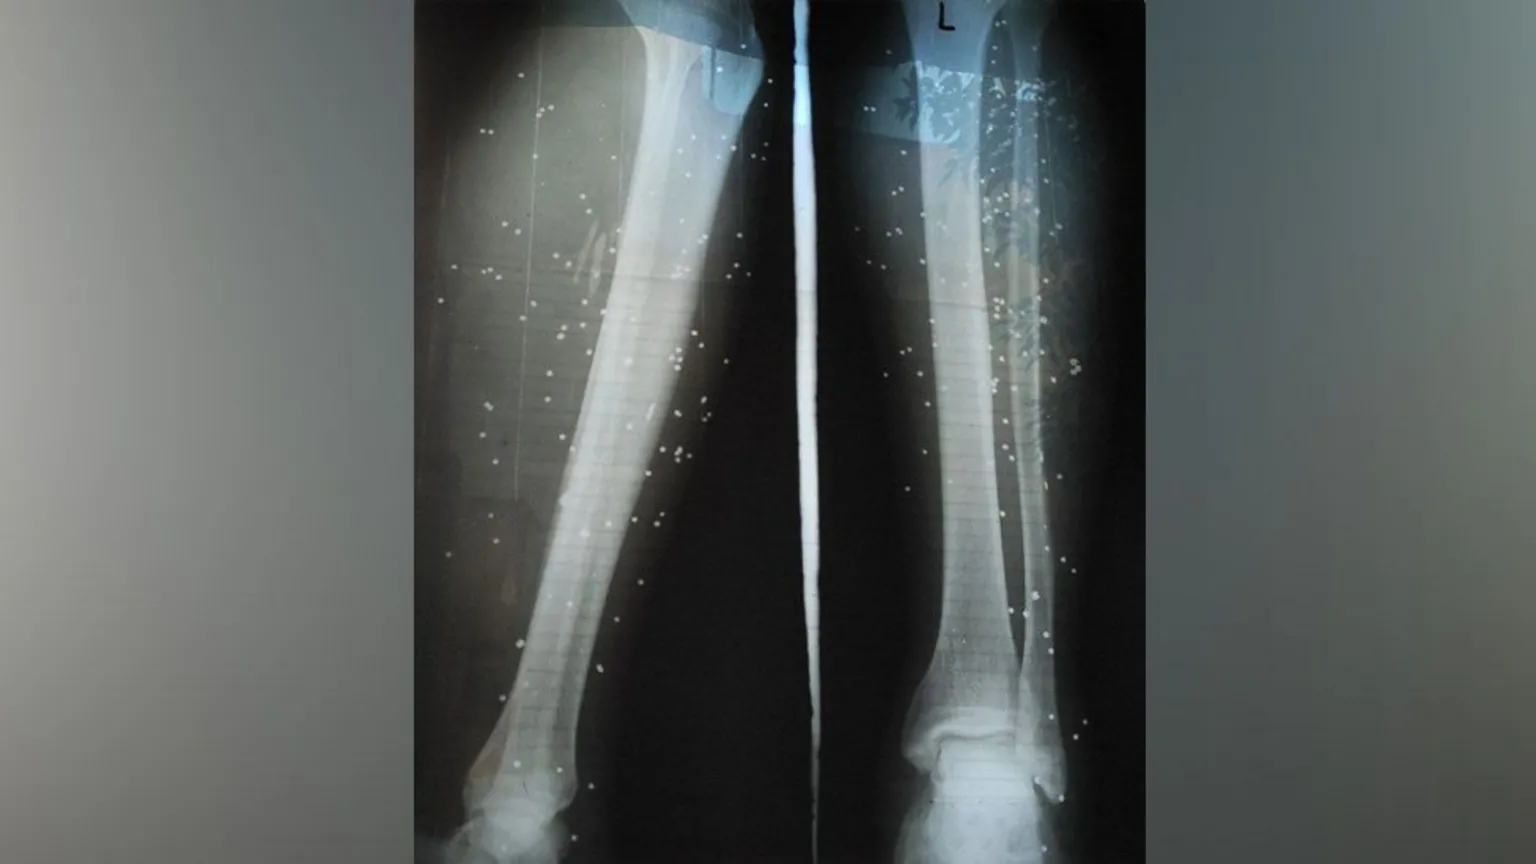

X-rays showed birdshot embedded in the legs of a wounded protester

They stayed at the couple’s home until it was almost dawn and then managed to find a doctor they knew, who cleaned the birdshot wounds on their legs, according to Tara.

She said a surgeon was later able to remove some of the birdshot at home but warned them: “They cannot all be removed and will remain in your bodies.”